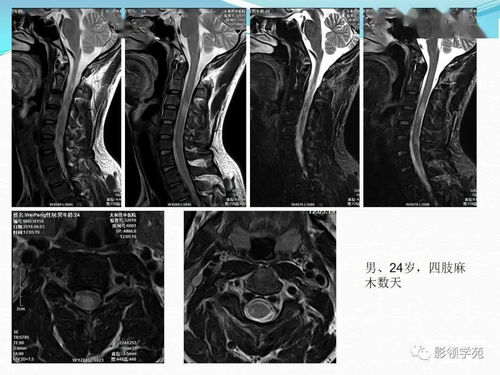

头晕要进行的检查包括颈动脉和椎动脉的彩超,通过这一检查我们可以了解血管状况,看是否存在狭窄或堵塞等问题。还需要进行颈部和颅脑的CT或磁共振检查,以排除颈椎病或脑梗死等疾病的可能。血生化检查也是必不可少的,它可以检测血糖、血脂等指标,帮助我们了解身体的整体状况。血常规检查可以了解是否存在贫血等问题。